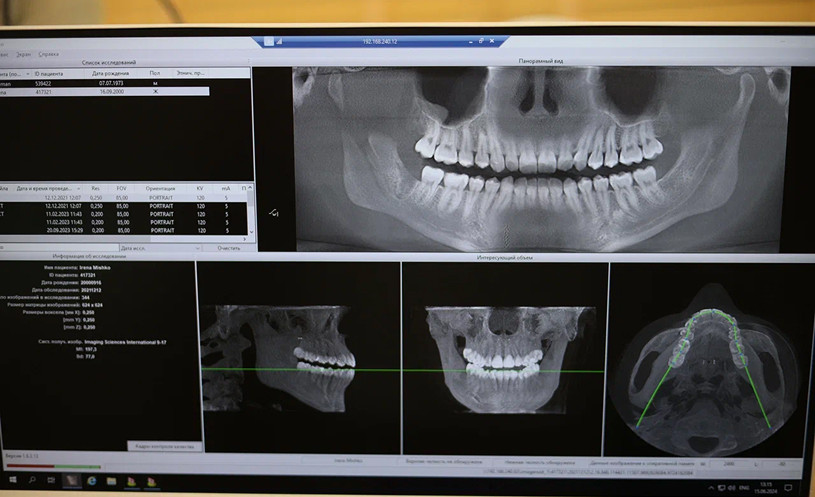

Для изучения расположения челюстей дантисты используют такие методы:

- Телерентгенограмма. Пациента направляют на рентген черепа в боковой проекции. На таких снимках сразу видны проблемы с челюстями и зубами.

- Изготовление гипсового слепка челюстей. Слепок делают для уточнения взаимного расположения зубных рядов. На слепке видны размеры, длина и ширина рядов, нюансы смыкания резцов.